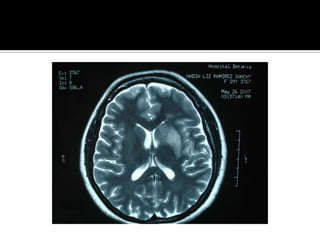

¿Pregunta 2?¿Cual es la localizacion y magnitud de la lesion?Respuesta: TAC o RM

Pregunta 3¿Cuál es la naturaleza ,localizacion, y gravedad de la lesion?Respuesta: clinica y Neuroimagen

¿Pregunta 2?¿Cual esla localizacion y magnitud de la lesion?Respuesta: TAC o RM

Pregunta 3¿Cuál esla naturaleza ,localizacion, y gravedad de la lesion?Respuesta: clinica y Neuroimagen